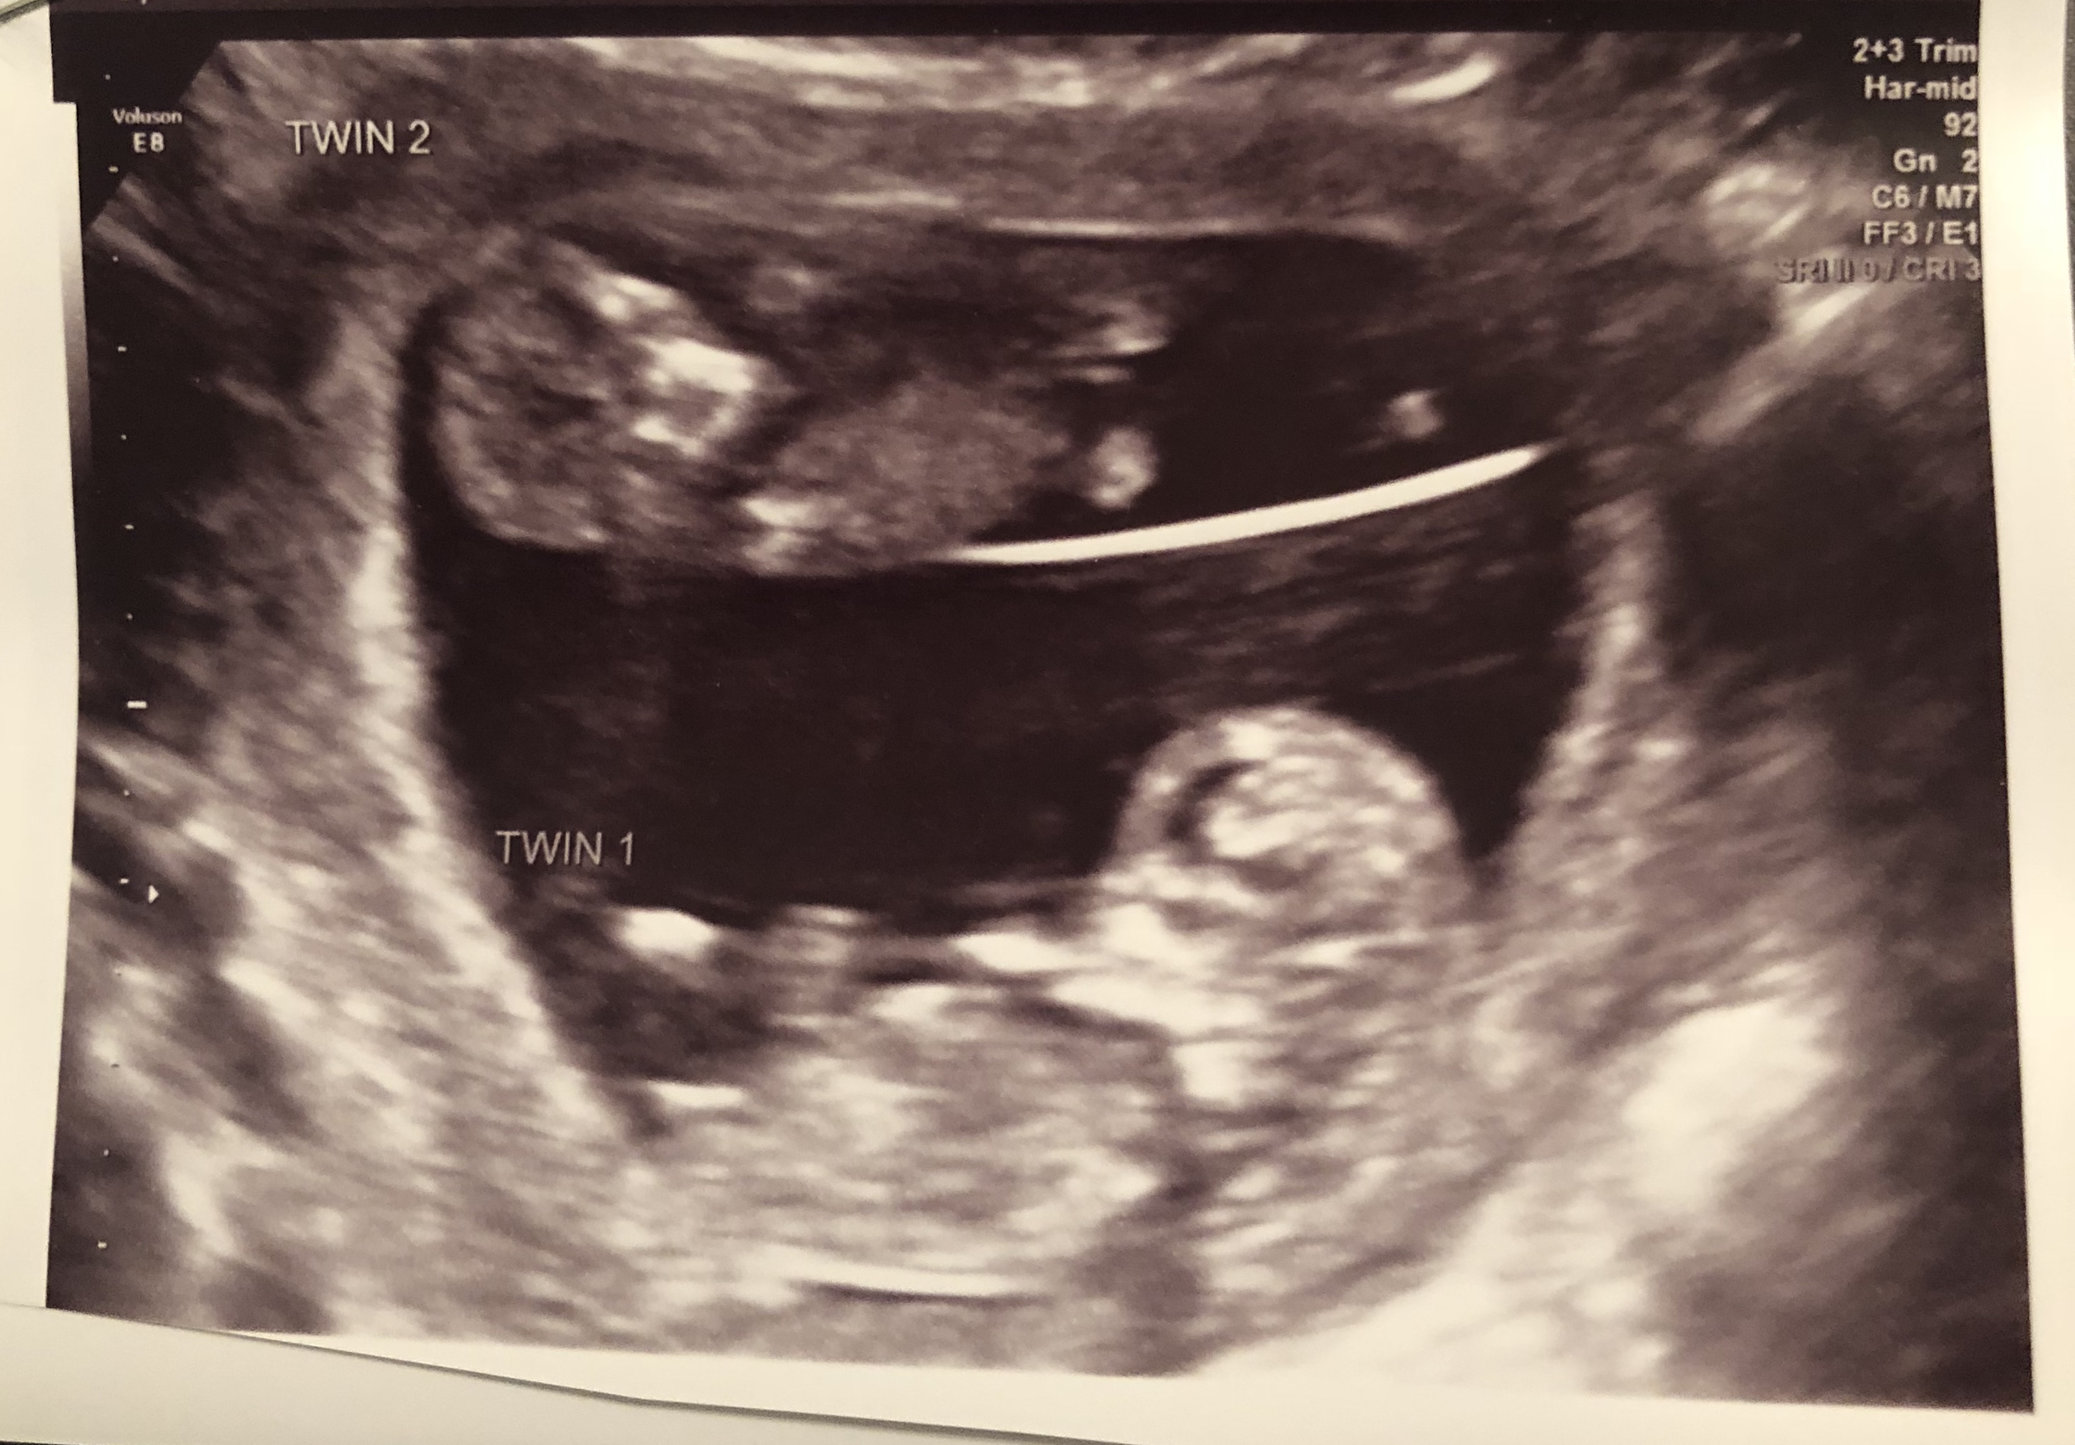

• We got one at 8 weeks. (Currently 11 weeks+4days) I didn't want to wait till later since my past history this year! My boyfriend,  6 year old daughter and me are so excited!